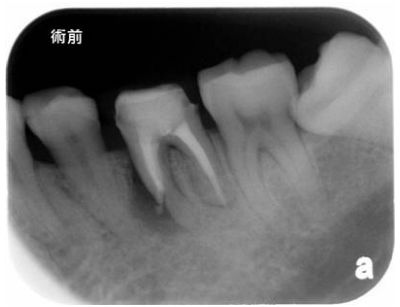

21.病患是由診所醫師轉診到教學醫院牙髓病科,尋求左下第二大臼齒後續的根管治療,下圖為X光 片檢查影像。對於左下第一大臼齒的問題,接受轉診的牙髓病科醫師應如何處理?

(A)除非左下第一大臼齒有臨床症狀,否則不需告知病患或轉診醫師 (B)若病患或轉診醫師未要求瞭解其他非轉診牙齒的狀況,則不需告知 (C)不用告知病患,但應告知轉診醫師 (D)應同時告知病患與轉診醫師

22.依前述,下顎左側第一大臼齒之牙髓診斷是: (A)可逆性牙髓炎(reversible pulpitis) (B)不可逆性牙髓炎(irreversible pulpitis) (C)牙髓壞死(pulp necrosis) (D)正常牙髓(normal pulp)

23.承上題,王小姐下顎左側第一大臼齒牙根尖診斷(periapical diagnosis)是: (A)正常(normal) (B)急性根尖牙周炎(acute apical periodontitis) (C)慢性根尖牙周炎(chronic apical periodontitis) (D)急性根尖膿腫(acute apical abscess)

24.承上題,王小姐案例之緊急處置,下列何者較妥善? (A)不需處理,繼續追蹤即可 (B)在本次就診馬上完成根管清創 (C)去除齲齒並放置止痛藥綿,臨時填充保護 (D)作斷髓(pulpotomy)或部分牙髓切除術(partial pulpectomy)處理即可

25. 此病患的 第一小臼齒牙髓與根尖疾病診斷為何? (A)慢性牙髓炎(chronic pulpitis)合併正常根尖組織(normal apical tissue) (B)慢性牙髓炎(chronic pulpitis)合併無症狀根尖牙周炎(aymptomatic apical periodontitis) (C)牙髓壞死(pulp necrosis)合併無症狀根尖牙周炎(aymptomatic apical periodontitis) (D)牙髓壞死(pulp necrosis)合併無症狀根尖膿腫(aymptomatic apical abscess)